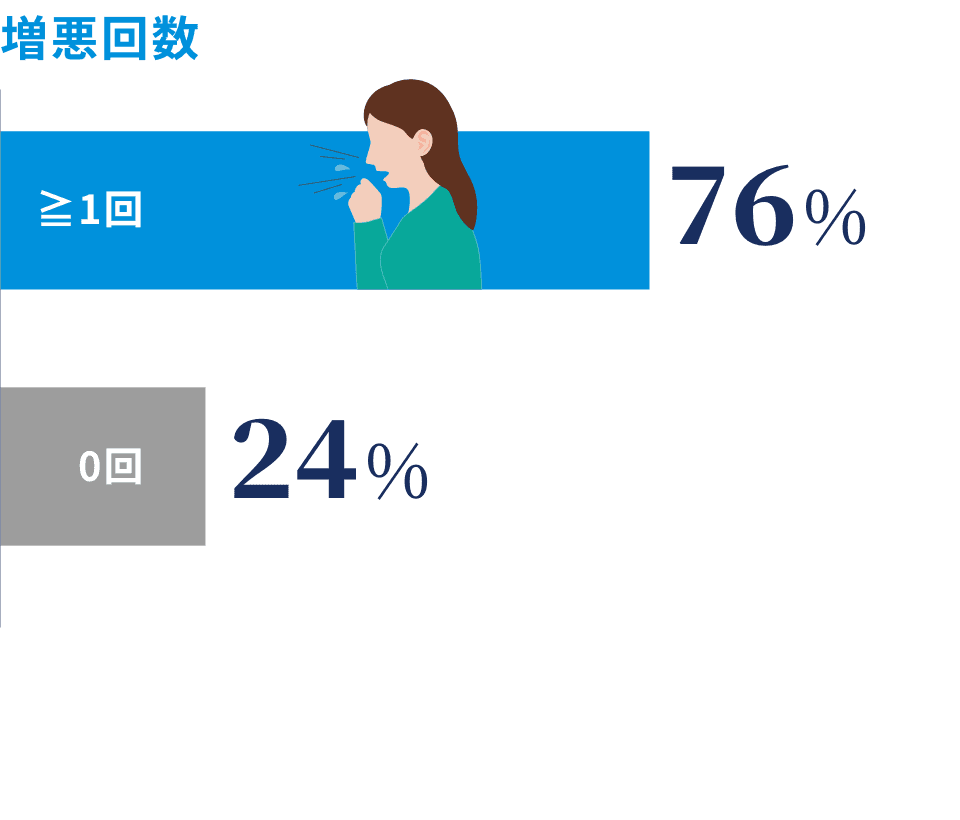

気管支拡張症は、不可逆的に進行する慢性炎症性疾患であり、近年世界的に有病率の増加が示唆され注目が集まっています。